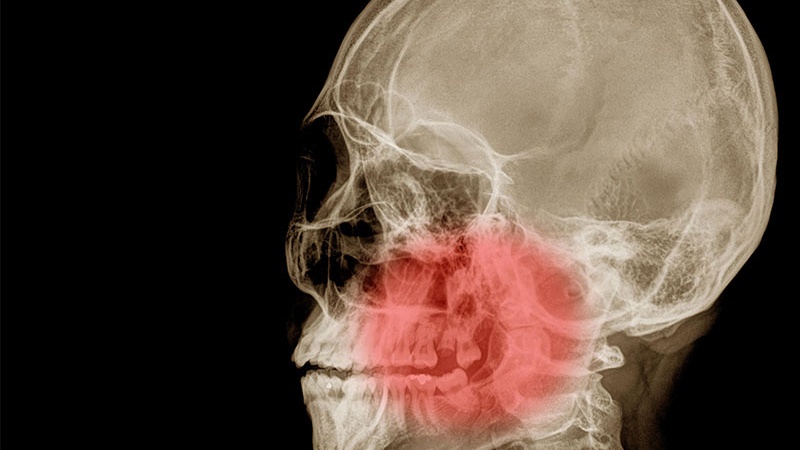

Chụp CT hàm mặt là một kỹ thuật hình ảnh tiên tiến, sử dụng tia X để tạo ra các hình ảnh chi tiết về cấu trúc xương, mô mềm trong vùng hàm mặt. Phương pháp này giúp bác sĩ chẩn đoán các vấn đề như viêm xoang, chấn thương, khối u, nhiễm trùng một cách chính xác và nhanh chóng.

Chụp CT hàm mặt đóng vai trò quan trọng trong quá trình chẩn đoán, điều trị các vấn đề về hàm mặt. Phương pháp này sử dụng tia X, các kỹ thuật hình ảnh để tạo ra các hình ảnh chi tiết của khu vực hàm mặt. Thông qua kết quả hình ảnh, bác sĩ có thể đánh giá, phát hiện các bệnh lý, tổn thương, hoặc các vấn đề khác liên quan đến hàm mặt một cách chính xác, nhanh chóng. Điều này giúp họ đưa ra phác đồ điều trị phù hợp, kịp thời để cải thiện sức khỏe và chất lượng cuộc sống của bệnh nhân.

Chụp cắt lớp vi tính hàm mặt là một trong những phương pháp chẩn đoán hình ảnh tiên tiến nhất được áp dụng trong lĩnh vực y học hiện đại. Phương pháp này không chỉ giúp bác sĩ chẩn đoán và đánh giá các bệnh lý liên quan đến vùng hàm mặt, mũi xoang, họng một cách chính xác, chi tiết, mà còn đóng vai trò quan trọng trong việc lập kế hoạch điều trị hiệu quả.

Khi một bệnh nhân có các triệu chứng hoặc nghi ngờ về bất kỳ vấn đề gì liên quan đến hàm mặt như sưng đau hoặc khó khăn trong việc hít thở, bác sĩ thường sẽ gợi ý thực hiện chụp CT hàm mặt. Phương pháp này cho phép tạo ra các hình ảnh 3D của khu vực hàm mặt, mũi xoang, họng với độ phân giải cao, giúp bác sĩ nhìn thấy rõ ràng mọi chi tiết, cấu trúc bên trong.

Thông qua việc xem xét các hình ảnh này, bác sĩ có thể phát hiện, đánh giá các vấn đề như viêm nhiễm, dị tật cấu trúc, polyp mũi xoang, viêm xoang, hay thậm chí là ung thư vùng hàm mặt. Từ đó ra quyết định về phương pháp điều trị phù hợp nhất cho bệnh nhân, từ việc sử dụng kháng sinh đến phẫu thuật chỉnh hình.

Ngoài ra, chụp CT hàm mặt còn đóng vai trò quan trọng trong việc theo dõi sự phát triển của bệnh, đánh giá hiệu quả phương pháp điều trị, đảm bảo rằng bệnh nhân đang được điều trị một cách tốt nhất có thể. Nhờ đó giúp giảm thiểu nguy cơ biến chứng, tăng cơ hội cho quá trình phục hồi của bệnh nhân. Nhờ vào công nghệ tiên tiến này, việc chẩn đoán và điều trị các vấn đề về hàm mặt ngày nay trở nên hiệu quả, an toàn hơn bao giờ hết.